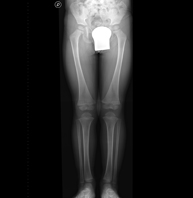

- Telemetry (Lower Limbs)

This technique uses X-ray rendered imaging to examine both lower limbs in their entirety, especially assessing the presence of dysmetria between the two.

- Limb X-ray

- Hip X-ray